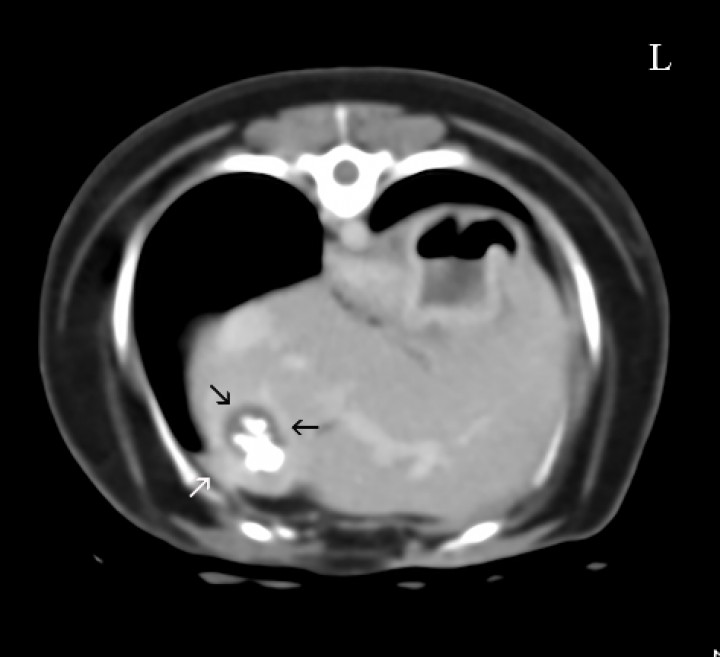

Se realizó una TC para caracterizar la fístula (Fig. 5) en la que se observaron cálculos en el interior de la vesícula biliar que ocupaban prácticamente toda la luz. Su pared estaba engrosada presentando adherencia al lóbulo hepático con la pared costal. Además, se apreció un nódulo en el lóbulo izquierdo y cálculos a nivel de la pelvis renal izquierda.

<p>Imagen de Tomografía Computarizada en ventana de tejido blando, post-contraste en plano transversal. Se visualizan cálculos en la vesícula biliar que ocupan prácticamente toda la luz y la pared engrosada (flechas negras); el lóbulo hepático presenta adherencias con la pared costal (fecha blanca). L: Izquierdo.</p>

Imagen de Tomografía Computarizada en ventana de tejido blando, post-contraste en plano transversal. Se visualizan cálculos en la vesícula biliar que ocupan prácticamente toda la luz y la pared engrosada (flechas negras); el lóbulo hepático presenta adherencias con la pared costal (fecha blanca). L: Izquierdo.